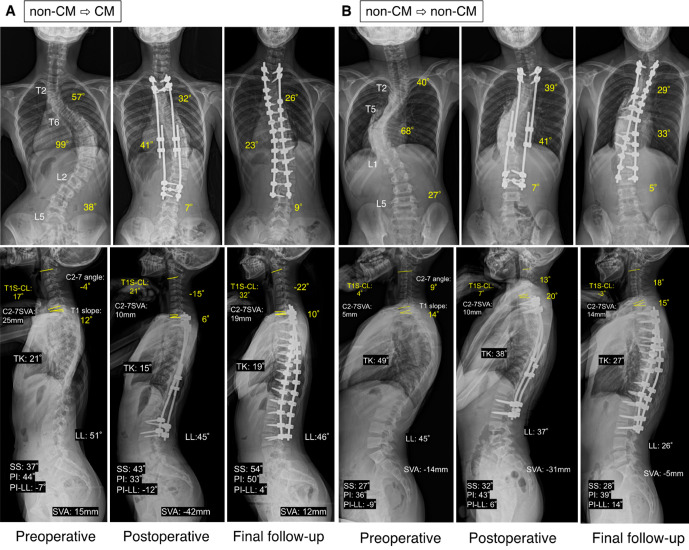

Methods: In this study, 28 patients who underwent GR and were followed up until final fusion or bone maturity were included. Standing whole-spine radiographs obtained before GR, after the initial GR surgery, and at the final follow-up were utilized to measure the radiographic parameters. Patients with one or more of the previously reported poor prognostic factors were included in the cervical malalignment (CM) group (n=13), and those with none of the factors were included in the non-CM group (n=15) at the final follow-up, which was followed by correlation analysis and multivariate logistic regression analysis.

Results: No significant change in sagittal alignment between preoperative and final follow-up measurements was found. Pearson correlation analysis revealed a significant positive correlation between the change in the C2-7 angle and T1 slope (T1S) or thoracic kyphosis and a negative correlation between the change in the C2-7 angle and T1S minus C2-7 angle (T1S-CL). The percentage of patients in the CM group increased from 25% preoperatively to 46% at the final follow-up but without significant change. The CM group had significantly smaller preoperative C2-7 angles and lumbar lordosis (LL) and larger T1S-CL and pelvic incidence minus LL (PI-LL) values than the non-CM group.

Conclusion: Smaller preoperative C2-7 angles and larger T1S-CL values were identified as risk factors for CM. Postoperative CM is more likely to occur in patients with reduced compensatory function to maintain preoperative cervical kyphosis.